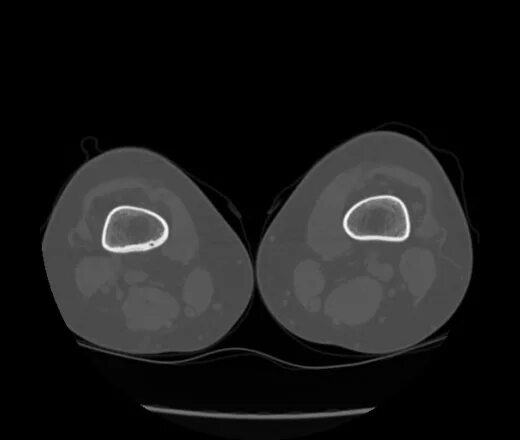

Фиброма кт